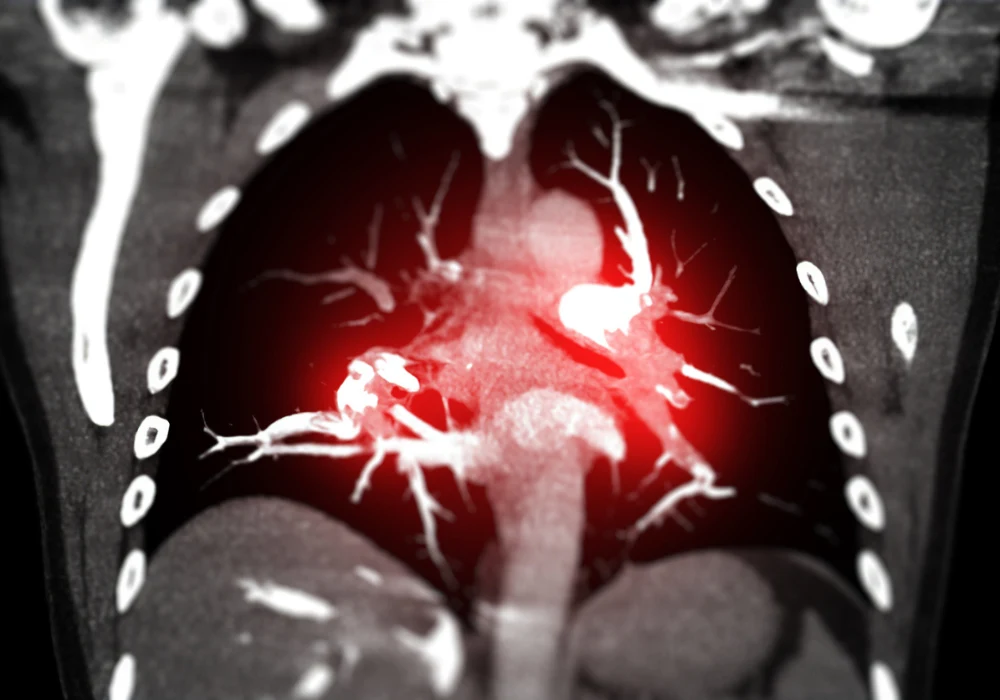

Accurate and timely diagnosis of acute pulmonary embolism (PE) is essential for initiating appropriate treatment and improving patient outcomes. Computed tomography angiography (CTA) has become the preferred imaging modality for PE when it cannot be excluded by clinical evaluation and D-dimer testing. Beyond detection, CTA provides vital prognostic information, identifies alternative diagnoses and informs advanced treatment planning. However, standardisation in CTA reporting remains lacking. To address this, leading societies in cardiovascular imaging and pulmonary care collaborated on a consensus statement outlining best practices for performing and reporting CTA in suspected PE.

To harmonise reporting and enhance clinical utility, the consensus defines a core set of CTA findings based on their prognostic value. A modified Delphi process identified eight “must-have” and three “nice-to-have” findings to be routinely included in CTA reports. These include clot location (central or subsegmental), signs of right ventricular (RV) overload such as the RV/left ventricular ratio, pulmonary artery trunk diameter, septum deviation, RV hypertrophy and bronchial artery dilatation. Findings such as intravascular webs, organised mural thrombi and pulmonary artery retraction help identify chronic thromboembolic pulmonary hypertension.

The consensus also offers standardised nomenclature to describe various types of filling defects and emboli. Structured reports incorporating this vocabulary improve interobserver consistency and support decision-making across care teams. A visual image atlas was developed to aid assessment, complemented by a lay-language version to enhance patient understanding.

CTA techniques have expanded with the integration of dual-energy CT (DECT) and photon-counting detector CT (PCD CT). These approaches enhance tissue differentiation and allow for perfusion imaging, which improves detection of peripheral clots and provides additional functional data. Subtraction imaging, which compares pre- and post-contrast scans, further refines pulmonary perfusion mapping. These innovations contribute to higher diagnostic accuracy, especially in complex or ambiguous cases.